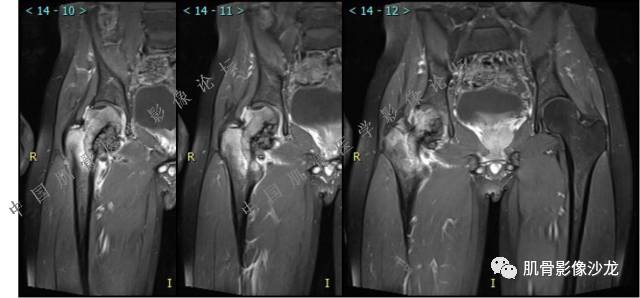

主诉:左髋疼痛1月余

现病史:患者1月余前无明显诱因出现左髋部疼痛,无明显活动受限,当地医院行X线检查,提示左股骨颈异常密度。遂来我院就诊。

既往史:曾患乙型肝炎,未正规治疗,目前无症状。

葛英霖 20:5 4 常规纤维类的多一些,冠状位没有看到明显脂肪。纤维结构不良、纤维组织细胞瘤、软粘纤之类。

夏威夷的风 20:55 大方向纤维类病变

Echo 20:55 考虑纤维类的依据是?

夏威夷的风 20:58 强化渐进性强化吧 边界清晰 里面也见线状低信号

飞鹰行动 21:01 良性纤维组织细胞瘤内部可以有少量脂肪

X(CT、MR)战警 21:01 泡沫细胞被吞噬后形成脂肪信号, bfh可以有脂肪条带样改变

Echo 21:04 总之这例就是各位老师说的硬化边明显,没有软组织肿块,没有侵犯,考虑良性病变,增强渐进性强化,所以考虑BFH